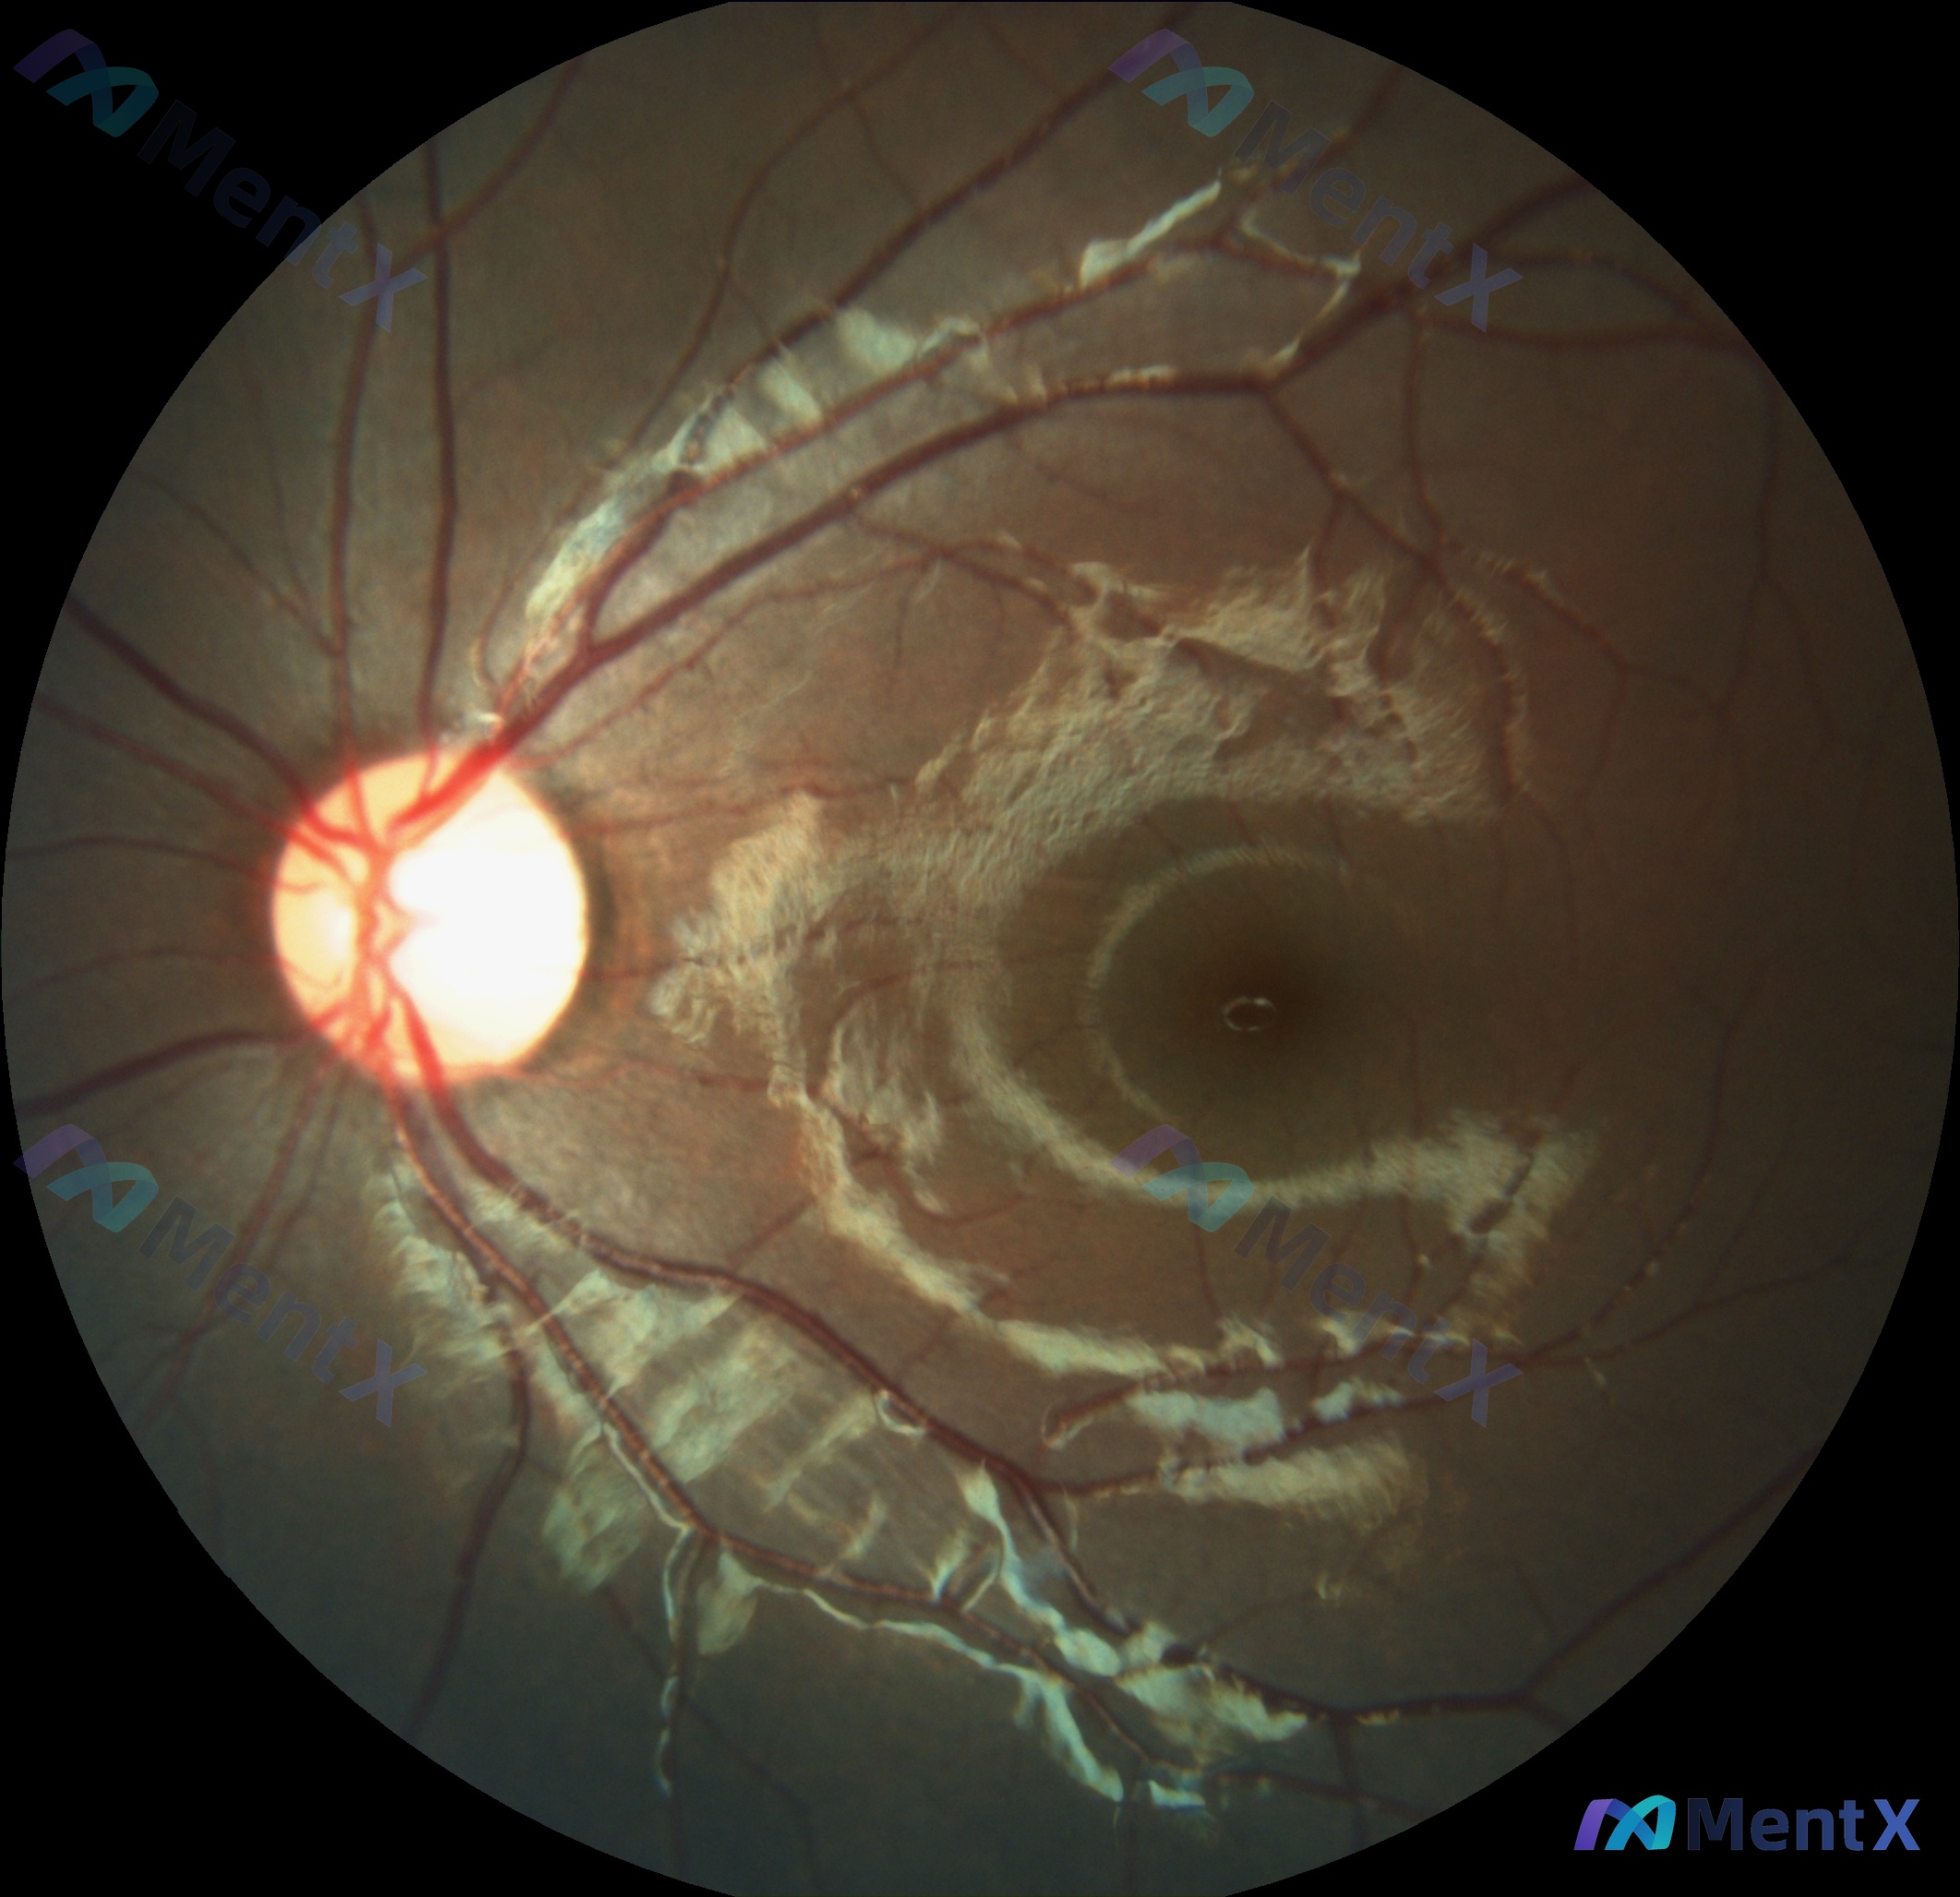

网上看到一张眼底彩照的影像分析资料,觉得这个渗出的表现很典型,也很容易有思路分叉,整理出来和大家讨论。 先把核心影像表现列出来: - 视盘:边界清,色泽正常,C/D比无扩大,无水肿/苍白 - 血管:动静脉比例约2:3,走行基本平直,无明显新生血管 - 关键异常:视盘颞侧至黄斑区之间,可见大片、连成环...

整理到一张眼底彩照的资料,先把客观影像表现放出来: - 视盘:位置、形态、颜色大致正常,杯盘比未见明显病理性扩大,盘沿也没看到明显异常 - 视网膜血管:走行基本自然,动静脉比例大致正常,没看到明显的血管闭塞、迂曲、截断或动静脉交叉压迫 - 黄斑区:中心凹反光可见,但颞侧有明显的黄白色蜡样硬性渗出,呈...